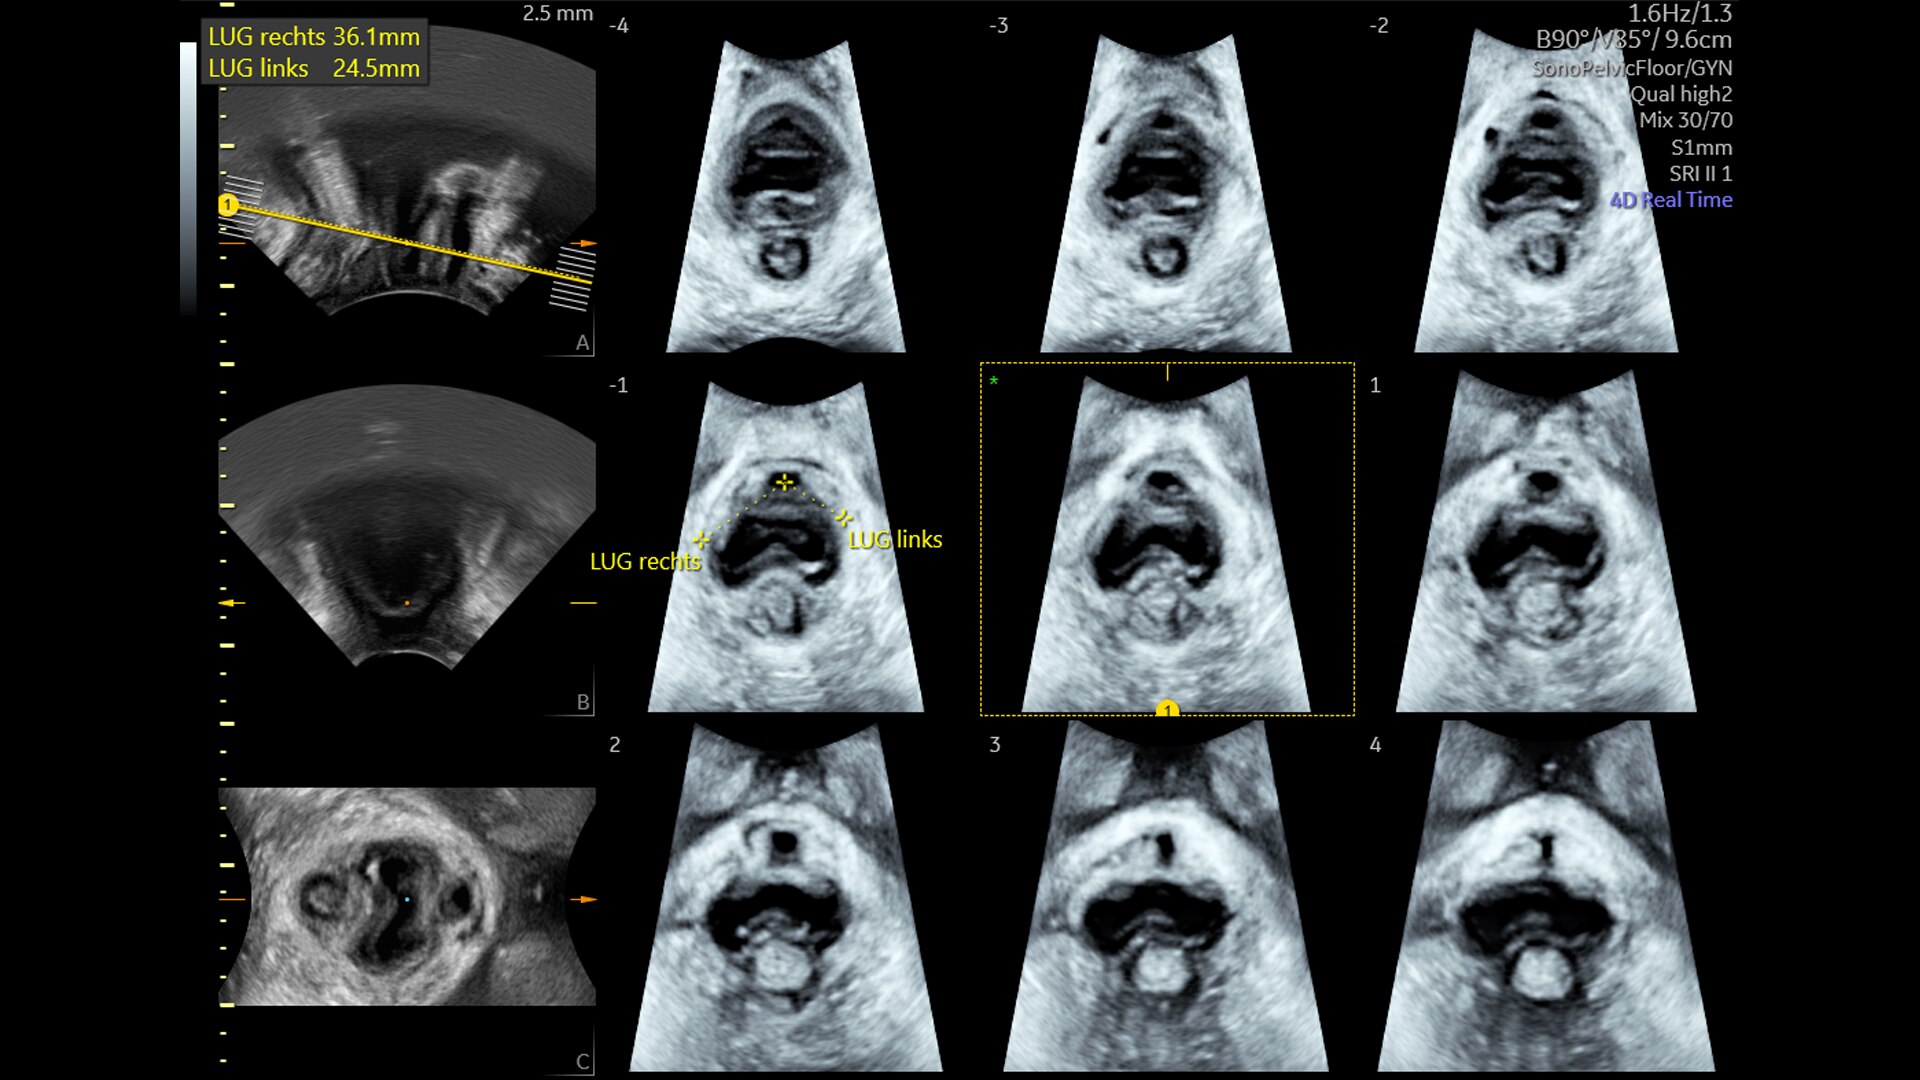

SonoPelvicFloor

Reduce exam time by up to 75% with SonoPelvicFloor. Simplify and speed up exams with automated plane alignment and automated measurements for more consistent reproducible results.